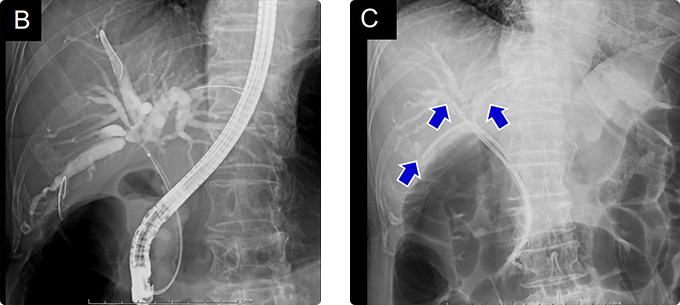

図7 門脈塞栓術後に拡大右肝切除を行った肝門部胆管癌-2

右門脈塞栓術後に右門脈は完全に閉塞しており、残肝体積は34%から42%に増大しました。

• 門脈塞栓術前の内視鏡画像 門脈塞栓術前

• 門脈塞栓術後の内視鏡画像 門脈塞栓術後

図8 門脈塞栓術後に拡大右肝切除を行った肝門部胆管癌-3

右肝切除+尾状葉全切除+肝外胆管切除・リンパ節郭清+胆管空腸吻合を行いました(手術時間8時間40分、出血量 700g、無輸血)。

組織学的な治癒切除が得られました。

図9 門脈塞栓術後に拡大右肝切除を行った肝門部胆管癌-4

治療経過と総ビリルビン値の推移を示します。内視鏡的ドレナージにより速やかに減黄しました。

術後は順調で5年無再発生存中です。